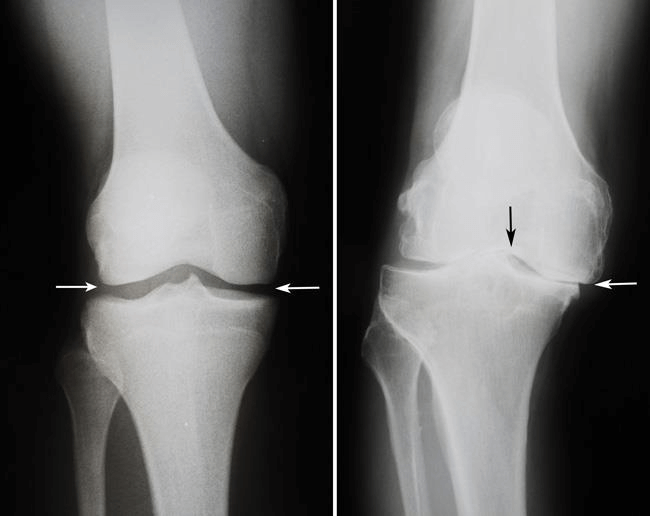

Εικόνα 12:(Αριστερά) Σε αυτήν την ακτινογραφία ενός φυσιολογικού γόνατος, ο χώρος μεταξύ των οστών υποδεικνύει υγιή χόνδρο (βέλη). (Δεξιά) Ακτινογραφία ενός παραμορφωμένου από αρθρίτιδα γόνατος που εμφανίζει σοβαρή στένωση του μεσάρθριου διαστήματος (βέλη).

Ακτινογραφίες: Βοηθούν στον προσδιορισμό της έκτασης της βλάβης και της παραμόρφωσης στο γόνατό σας.